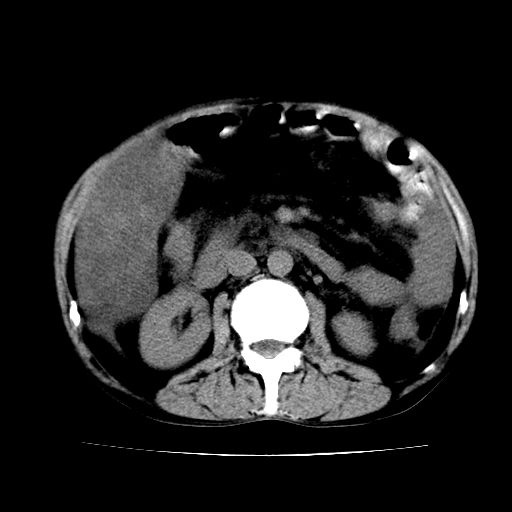

男,55岁,发现“肝硬化”5年,现腰疼、腹胀10余日,巩膜黄染、腹稍胀,肝肋下3指,质硬无压疼,移动性+,血生化:总胆、直胆、间胆均升高。

1.脂肪肝

2.腹水

3.肝脾肿大

4.肝癌?

建议增强

腹部病变,ct平扫如同隔靴搔痒,建议增强后上传资料。